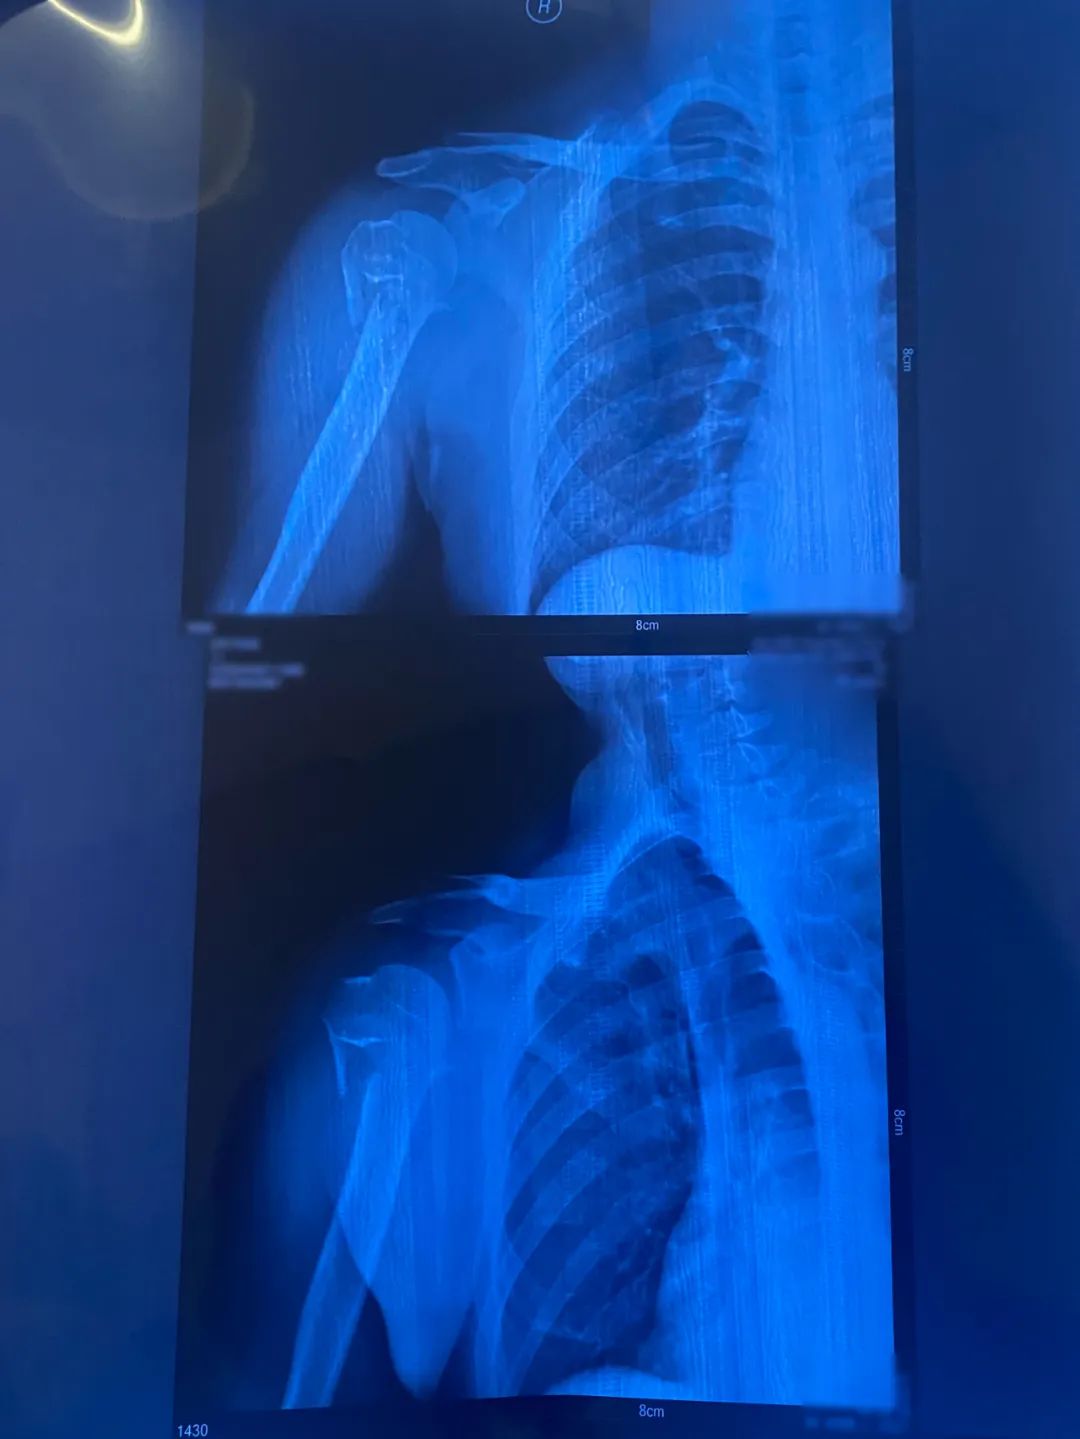

被诊断为

右肱骨外科颈粉碎性骨折

杨鹰术前CT图事后,同事前来探望受伤的杨鹰